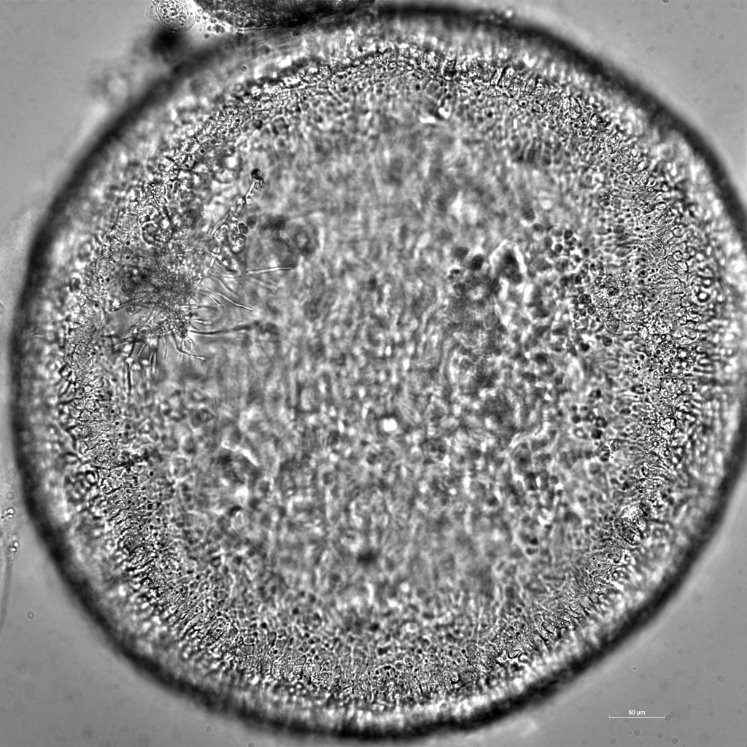

Microinjections

The ORGANOMICROLIFE LAB is elaborating novel strategies for organoid microinjection. Microinjections may be implemented for host pathogen interaction mechanistic studies, for drug discovery and cancer treatment.